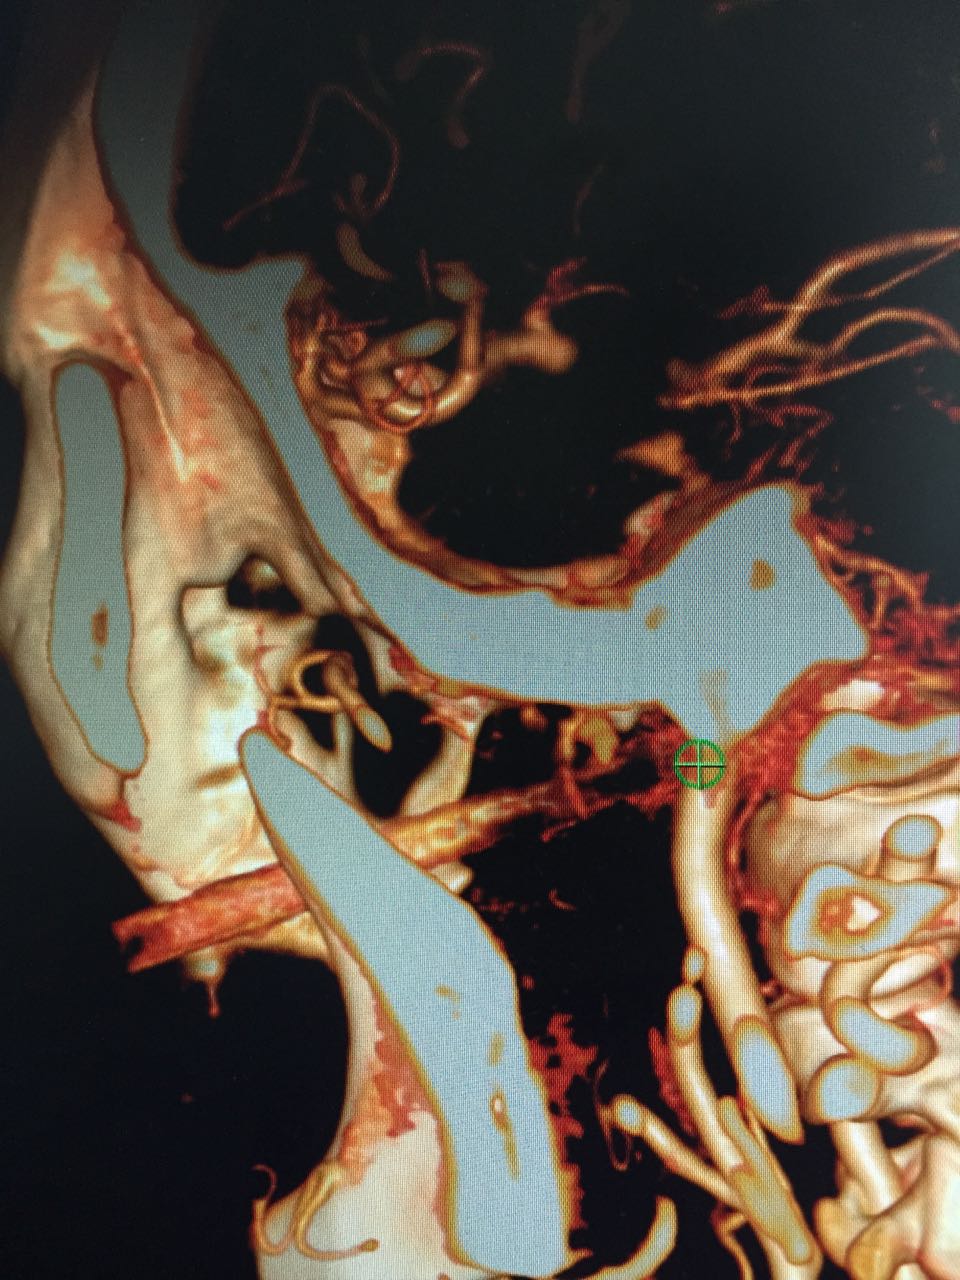

入院后立即完善术前的CTA检查,高分辨薄层CT以及三维重建结果进一步证实了谭国林教授的预判。长近10公分的竹棍从面颊部插入,避开眼球,紧贴颈内动脉壁插入颅底,并导致第一颈椎部分骨折,只差那么一点点就进颅内了。而且因为2个月的反复感染,动脉壁受侵蚀,动脉内大块的血栓形成,老人家随时都可能发生动脉破裂出血或者脑梗塞。

谭国林教授和蒋明副教授紧急组织术前讨论,确定手术入路和风险应对方式。根据影像学资料,经过仔细的讨论决定先从前方进路暴露异物,同时准备颈侧切开暴露,如果有颈动脉破裂随时结扎颈动脉。向患者家属详细交代手术风险后,患者及家属强烈要求手术排掉这颗随时引爆的“地雷”。